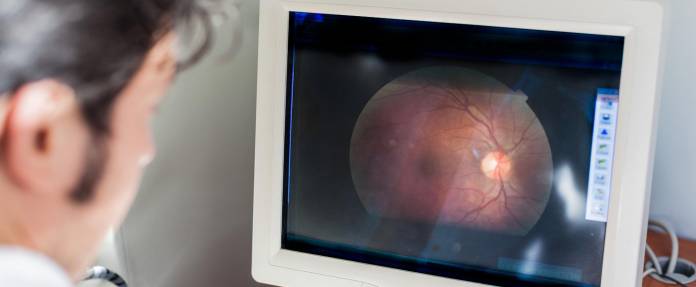

Eine Netzhautablösung (Amotio oder Ablatio retinae) hat ohne Behandlung eine schlechte Prognose. Die Ablösung kann sich ausdehnen und zur Erblindung führen. Um dies zu verhindern und möglichst viel Sehfähigkeit des betroffenen Auges zu erhalten, muss eine Operation zum Anlegen der Netzhaut durchgeführt werden. Mit dem Eingriff lässt sich meist ein Zustand schaffen, bei dem die Netzhaut stabil bleibt und das Sehvermögen nicht weiter abnimmt. Häufig lässt sich das Sehen damit wieder etwas verbessern. Voraussetzung dafür ist, dass die Ablösung nicht den mittleren Bereich der Netzhaut betrifft. Eine Einschränkung im Sichtfeld bleibt trotzdem meist bestehen.

Wenn eine Netzhautablösung nicht oder nicht rechtzeitig behandelt wird, weitet sie sich nach und nach auf angrenzende Bereiche aus. Immer größere Teile des Gesichtsfeldes werden mit einbezogen und fallen für das Sehen aus. Schließlich erreicht die Ablösung das Zentrum der Netzhaut, an der das Scharfsehen stattfindet. Wenn sich dort die Netzhaut abtrennt, kommt es zu einem erheblichen Verlust an Sehschärfe (Visus). Im weiteren Verlauf kann das Auge komplett und unwiederbringlich erblinden.